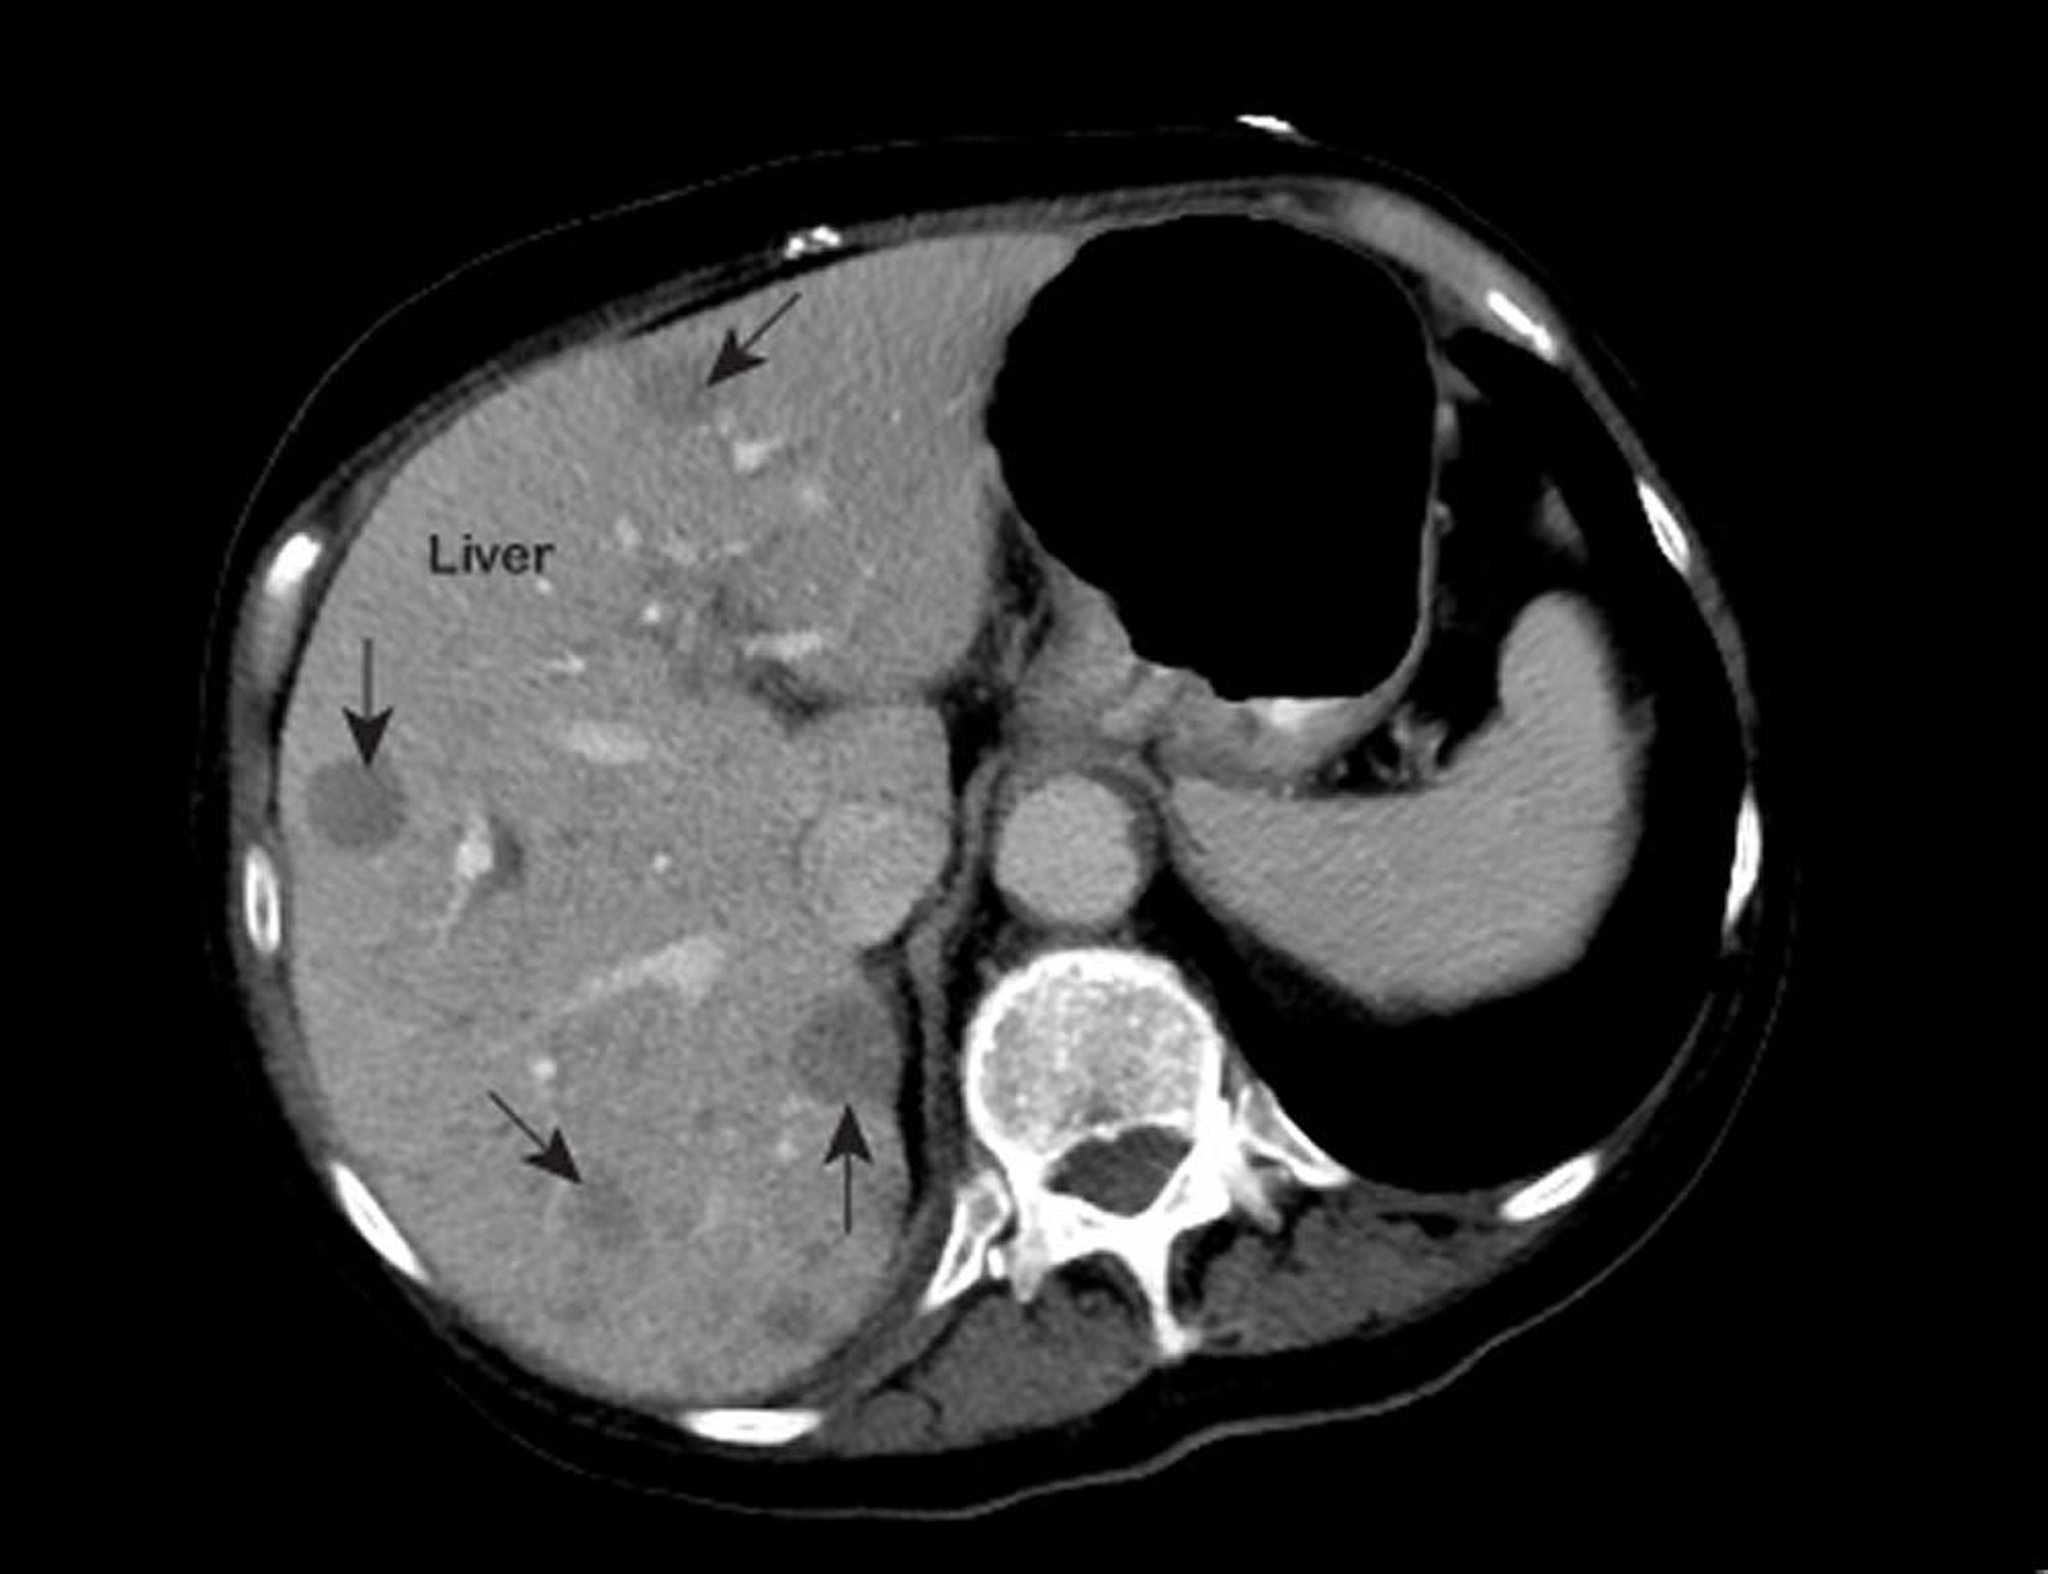

سرطانُ الكبد النَّقيلي Metastatic Liver Cancer

صورة رنين مغناطيسي للصدر تُظهر مناطق غير طبيعية في داخل الكبد (اتجاه الأسهم).تُعد هذه العلامات نمطية للإصابة بسرطان الكبد النقيلي.

جرى استخدام الصورة بعد موافقة أصحابها Patrick O’Kane, MD.